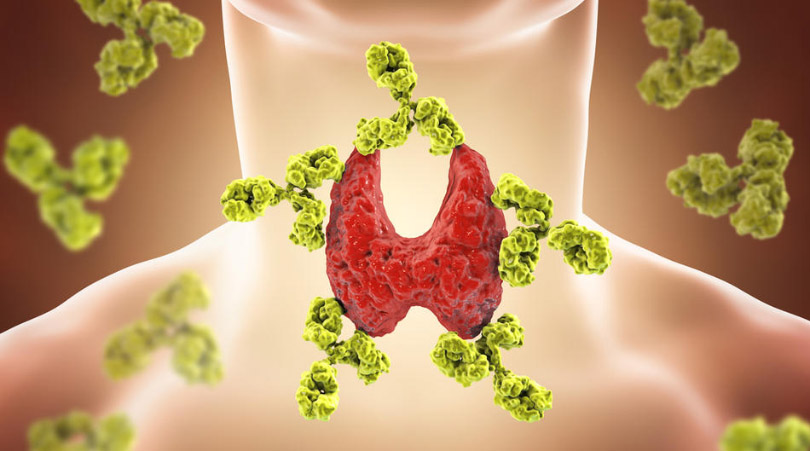

1. Štitnjača je važan organ

Štitnjača izravno ili neizravno kontrolira gotovo svaku pojedinu funkciju u tijelu. Svakoj stanici u našem tijelu potreban je hormon štitnjače, zbog čega je vrlo važno voditi računa o tome da u organizmu uvijek imamo zdravu i uravnoteženu količinu ovog hormona.

2. Problemi sa štitnjačom utječu na cjelokupno zdravlje

S velikom moći dolazi velika odgovornost, a štitnjača nije iznimka. Nažalost, postoji mnogo načina na koje funkcija ove žlijezde može biti poremećena te niz zdravstvenih stanja koja spadaju u kategoriju bolesti štitnjače. Najpoznatiji su hipotireoza (neaktivna štitna žlijezda), hipertireoza (kada je prekomjerno aktivna), Hashimoto (autoimuni poremećaj koji napada štitnjaču, izazivajući hipotireozu) i Gravesova bolest (autoimuni poremećaj koji uzrokuje hipertireozu). Postoje i četiri vrste karcinoma štitnjače: papilarni, folikularni, medularni i anaplastični.